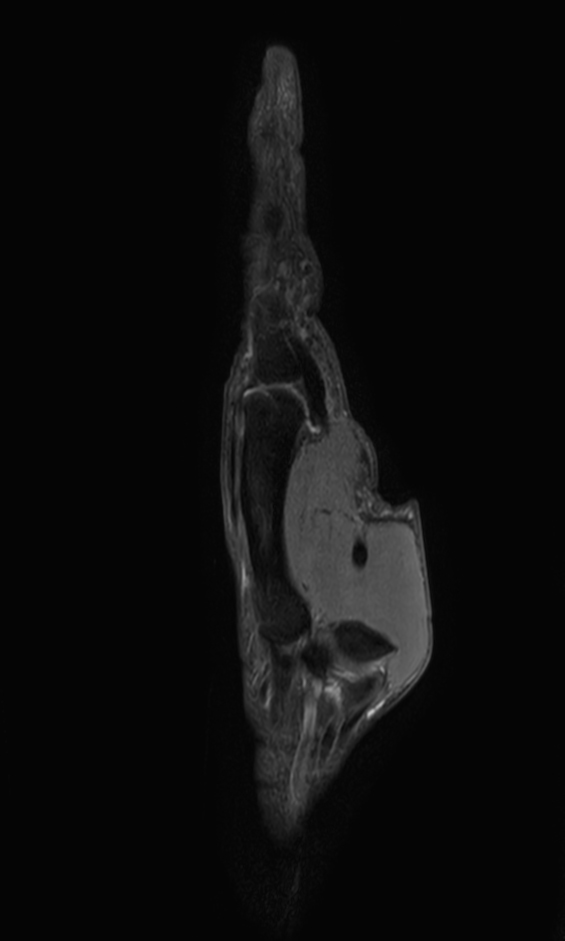

Sagittal PDw TSE mDIXON XD (In Phase)